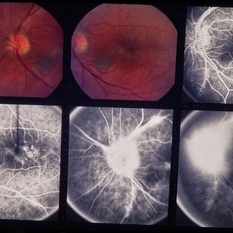

PDR

Jan 24 2014 by Howard Schatz, MD

64-year-old white female. 20/25 and 5/200.